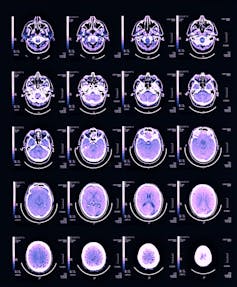

Neuroscientists have long assumed that neurons are greedy, hungry units that demand more energy when they become more active, and the circulatory system complies by providing as much blood as they require to fuel their activity. Indeed, as neuronal activity increases in response to a task, blood flow to that part of the brain increases even more than its rate of energy use, leading to a surplus. This increase is the basis of common functional imaging technology that generates colored maps of brain activity.

Luckily, the brain leaves behind evidence of its energy use through the pattern of the vessels that distribute blood throughout it. I figured I could look at the density of capillaries – the thin, one-cell-wide vessels that transfer gases, glucose and metabolites between brain and blood. These capillary networks would be preserved in the brains in my freezers.

What I found was clear evidence for the latter. For both mice and rats, capillary density makes up a meager 2% to 4% of brain volume, regardless of how many neurons or synapses are present. Blood flows in the brain like water down rivers: where it can, not where it is needed.

If blood flows regardless of need, this implies that the brain actually uses blood as it is supplied. We found that the tiny variations in capillary density across different parts of dead rat brains matched perfectly with the rates of blood flow and energy use in the same parts of other living rat brains that researchers measured 15 years prior.